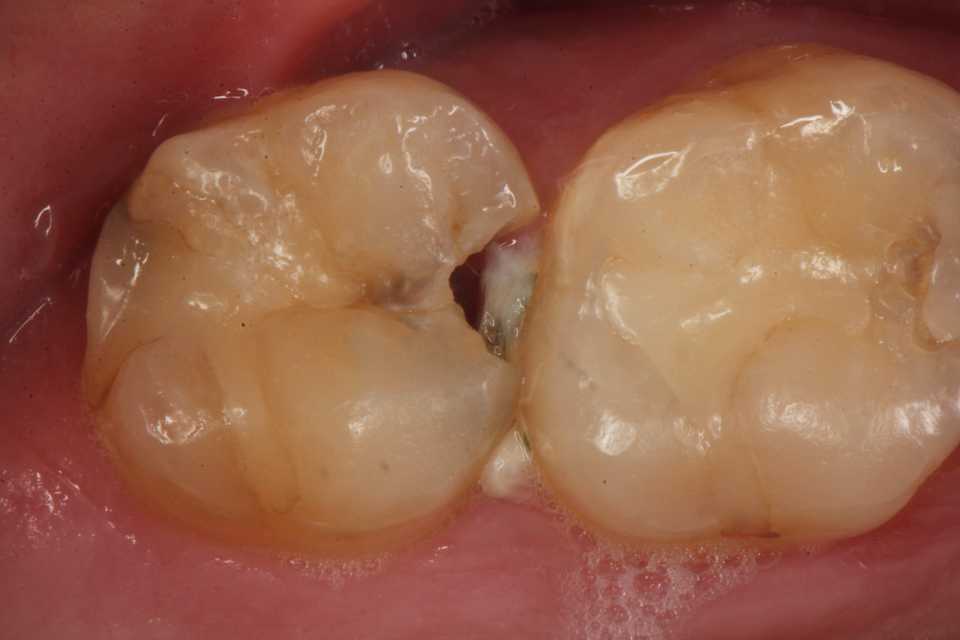

50代女性、左上5-7ブリッジ脱離、7番2次カリエス+Per(根尖性歯周炎)、強度の外傷性咬合この方、ひどい食いしばりで歯が壊れてしまう。噛み合わせの左下7番も歯冠が崩壊しつつある。7番はブリッジが脱離していて、内部は虫歯でドロドロ。Perつまり根管充填が緊密ではなく、歯根内部は細菌だらけで根の周りにはひどい炎症がある。まずはレントゲン写真から。7番の歯根の周りが炎症で黒くなっているのが分かると思う。ブリッジを全部外すと咬合が狂うので、とりあえず7番だけカットして内部を見てみた。根管充填材が見えるところまで軟化象牙質を除去して、3MIX+α-TCPを入れて根管内部を殺菌することにした。根管充填材の周りは黒くなっているのが見えると思うが、これは硫酸塩還元細菌の代謝産物の硫化鉄:FeSで、理想に反して根管充填材はゆるゆるの緊密充填ではないことを示している。このような状況は普通のことだ。歯根内部は細菌だらけということだが、ゆるゆるだから根管充填材を全部除去する必要もない。ゆるゆるの隙間から3MIX(抗菌剤)は浸透し根管は殺菌される。外傷力を弱めるために咬合調整を繰り返している。コア部分は隙間に細菌由来の黒色物質FeSがこびりつき、真っ黒。ポンティック下も細菌のコロニーでドロドロ歯質は残っているように見えるかもしれないが、ボンディング材が効く程度に軟化象牙質(虫歯)を除去すると、残根状態になる。つまり通常治療では抜歯しかないということだ。しかもPerでグラグラの動揺度2〜3、垂直性同様有りだ。とてもこのままではブリッジの支台には使えそうもない。ピンク色の根管充填材が見えると思うが、周りは真っ黒だ。その真っ黒になった隙間から細菌は侵入するし、3MIXも浸透する。こうではない緊密な根管充填治療は垂直加圧法でしか見られない。3MIX+α-TCPCR(ダイレクトボンディング)で覆う。これでないと微小漏洩が起こり失敗する。丸い形はラウンデッド・コアと呼び、この形が咬合力を内向きに集中させ歯根を守る。ポストは歯根の外側にこじるような応力を生じるので歯根を壊してしまいやすい。補綴物が必要な時はピンレッジで維持力を得る。これはCAD/CAMでは作れないだろう。これで2〜3週間様子をみる。外傷性咬合のコントロール(ナイトガードや行動療法)をしながら。つづく